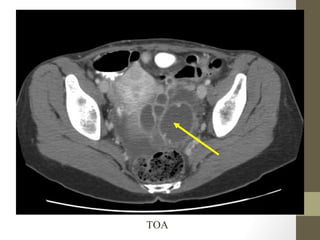

TOA

Radiology- CT Scan

• Detect leaking AAA (in stable patient)

• Evaluate for renal calculi, appendicitis, perforation (free air),

diverticulitis, abscess, mesenteric ischemia, masses, obstruction